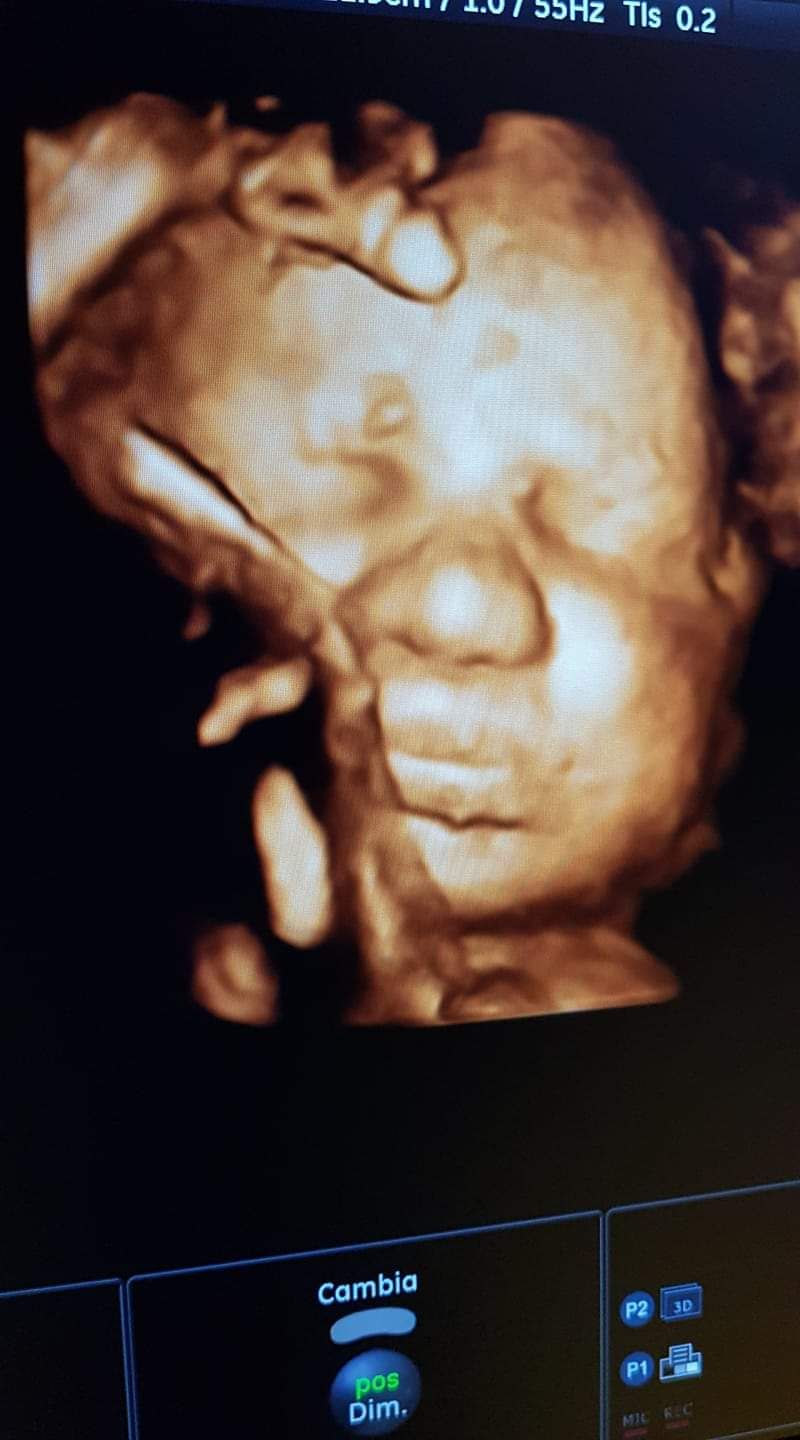

Foto e video